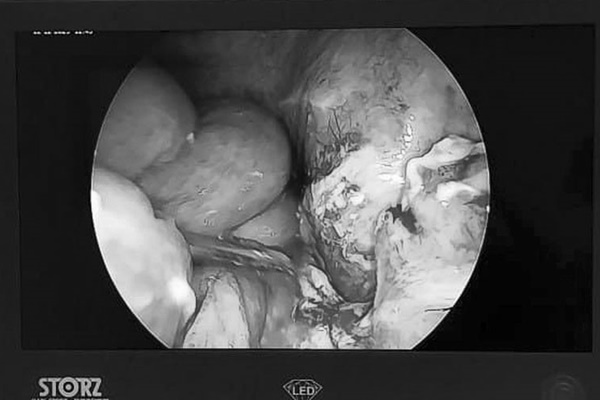

Sau khi được thăm khám và làm xét nghiệm, bệnh nhi được chẩn đoán viêm phúc mạc do viêm ruột thừa vỡ. Ngay lập tức, các bác sĩ tiến hành phẫu thuật cấp cứu nội soi cắt ruột thừa viêm, rửa sạch ổ bụng, đặt dẫn lưu ổ bụng. Do đến muộn nên tình trạng ổ bụng bẩn, các quai ruột dính nhiều khiến quá trình phẫu thuật rất khó khăn, mất nhiều thời gian.

Đồng thời sau phẫu thuật, tình trạng bệnh cũng diễn biến phức tạp, bệnh nhi nôn nhiều, chướng bụng, thời gian ăn uống trở lại và có lưu thông tiêu hóa lâu. Hiện tại, các bệnh nhi đã tạm ổn định, tuy nhiên do nhập viện muộn nên việc điều trị tiên lượng sẽ kéo dài, tốn kém trong chi phí điều trị, ảnh hưởng đến sức khỏe, học tập của bệnh nhi và công việc của gia đình.